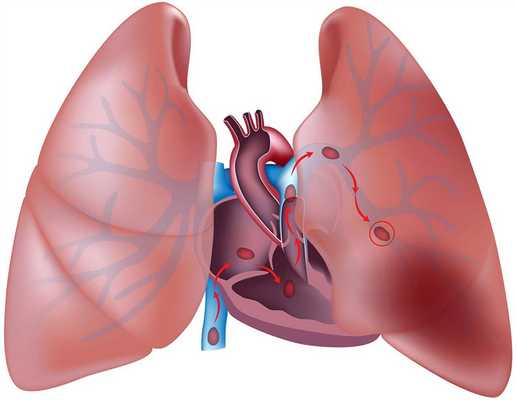

Тромбоэмболия легочной артерии (ТЭЛА) — тромботические массы в системе легочных артерий.

Источник эмбола обычно в правых камерах сердца, глубоких венах нижних конечностей и таза.

Обрывки от сидящих тромбов заносятся в легкие и закупоривают большие или малые ветви ЛА.

Тромбоэмболия легочной артерии (ТЭЛА) — внезапная закупорка ветвей или ствола легочной артерии тромбом (эмболом), образовавшимся в правом желудочке или предсердии сердца, венозном русле большого круга кровообращения и принесенным с током крови. В результате ТЭЛА прекращается кровоснабжение легочной ткани. Развитие ТЭЛА происходит часто стремительно и может привести к гибели больного.